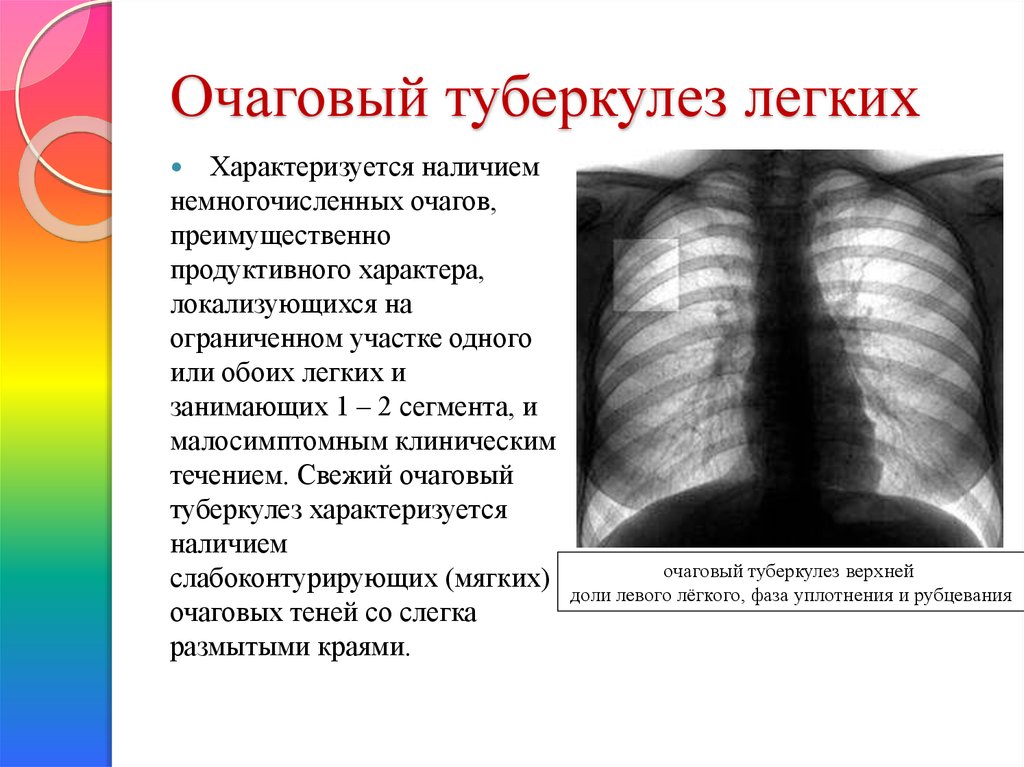

Очаговый и инфильтративный туберкулез презентация - 94 фото